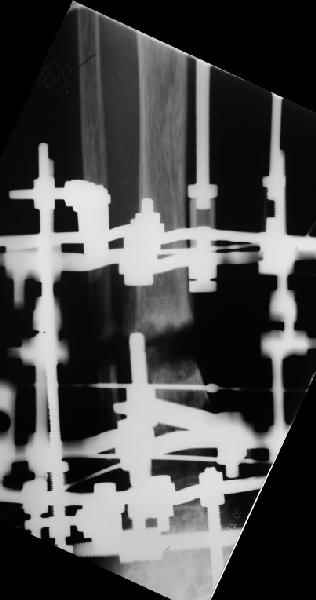

> In attachment - x-rays at the end of alignment, the surgery, and

> result. The nail was cut to 23 cm. Four 45 degree holes were

> pre-drilled at the distal nail tip. The nail was locked statically

> after some impaction.

Amazing! How can you find the pathway of the nail through all those wires and the distal screws through so much hardware?

NL> Amazing! How can you find the pathway of the nail through all those wires

NL> and the distal screws through so much hardware?

Some wires were intentionally inserted to leave needed space for the nail, some were removed at the moment of nail insertion. I inserted one distal screw and then removed the frame, then inserted rest ones.